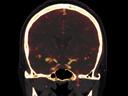

More and more radiologists are relying on the rich diagnostic possibilities offered by True Dual Energy imaging on Siemens Healthineers' CT scanner fleet ranging from SOMATOM® Scope Power up to the outstanding SOMATOM Force.

The question is: What makes True Dual Energy stand out? Look for these three criteria: crisp images with the option for even sharper contrast and significant artifact reduction; no extra dose in either Single Source or Dual Source Dual Energy scans, and a broad applicability for virtually all clinical questions and patients.

Discover Dual Energy (DE) spectral imaging. It’s the difference between images and answers. Visualization and characterization. Qualification and quantification. Built into all of our CT scanners, it delivers powerful performance, incredible versatility for your entire patient population, and exceptional ease-of-use – all while integrating seamlessly with your current workflow.